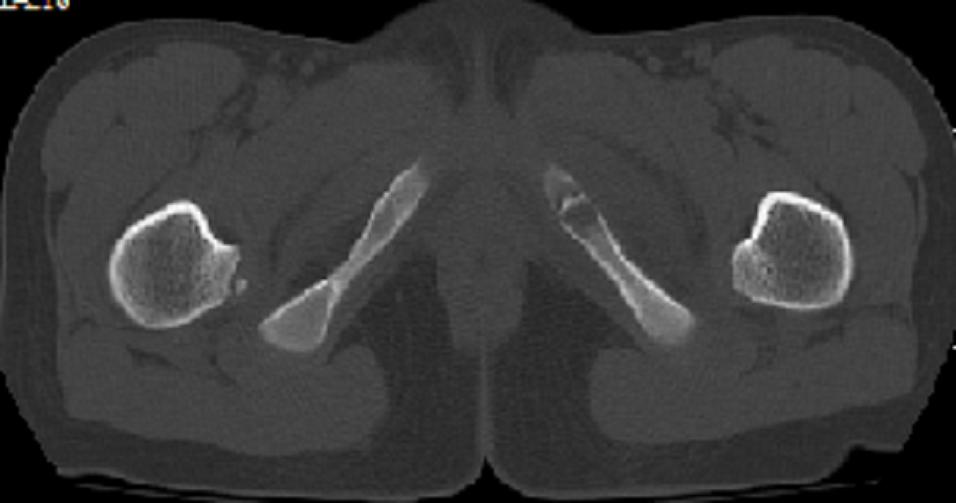

以下是引用zxd95在2008-7-2 10:06:00的发言:[br]左耻骨下支局部骨质破坏,内见小条状小骨片,周围肌间隙模糊,左闭孔内外肌肿胀。[br]儿童患者,首先考虑结核性,以骨质破坏为主(其内小条状小骨片解释为死骨)。[br]鉴别:[br]1、化脓性病变以增生为主;[br]2、肿瘤性病变:良性肿瘤不会有周围软组织的肿胀、模糊;恶性肿瘤病变骨皮质破坏、中断;[br]3、肿瘤样病变:一般也无周围软组织的改变。[br]建议查肺部及结核相关实验室检查。

以下是引用dyqct在2008-7-2 15:38:00的发言:[br]左坐骨与耻骨交界处膨胀性溶骨性病变,周围软组织略肿胀,边界不清。[br]发生在这个年龄组该部位最常见的一种发育变异,可以出现此种改变。另外感染不除外,建议定期复查。